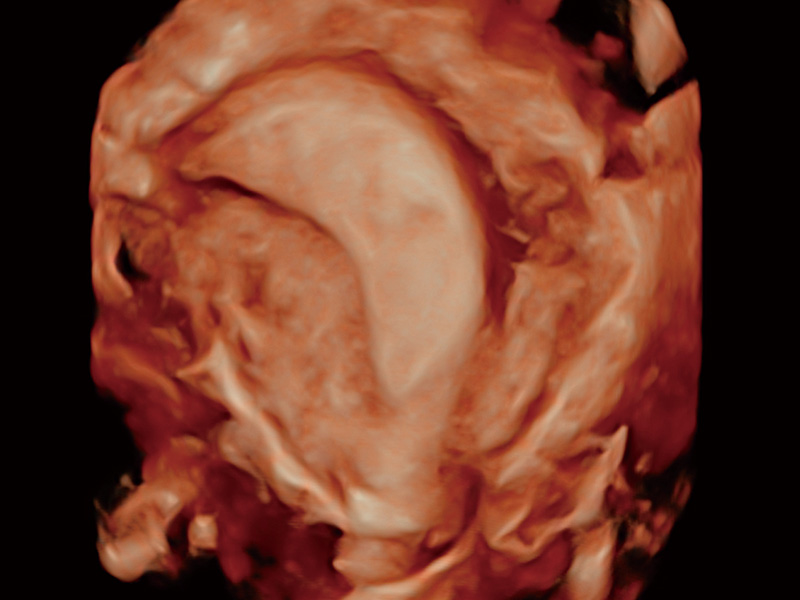

腔内容积探头

腔内三维成像技术获得显著提升,超大扇角在满足日常基础扫查的同时,支持卵泡自动测量及多种三维渲染模式,为您提供更多的诊断信息,尤其是在子宫畸形的诊断,内膜及肿瘤占位观测中起到了重要的作用。

临床图

中央型宫腔粘连

单角子宫